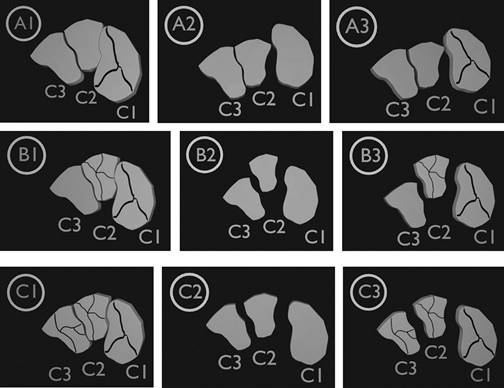

Mehlhorn y colaboradores (2016), tras la revisión de 55 casos de lesiones cuneiformes desde 1967 a 2014, a los que suman cinco casos propios, proponen una clasificación con parámetros semejantes a la establecida por la AO. En su sistema de clasificación propuesto, establecen como A: lesiones de un solo hueso cuneiforme, B: lesión de dos cuneiformes y C: lesión de los tres cuneiformes. Además, les asignan el numero 1 al 3, de acuerdo con: si la lesión es una fractura se representa con el número 1, en caso de luxación con el número 2 y en lesiones combinadas con luxofractura, el número 3 (Figura 1).20

Figura 1: Representación esquemática de la clasificación de Mehlhorn y colaboradores. A1, A2 y A3) Fractura, luxación y luxofractura involucrando un solo hueso cuneiforme. B1, B2 y B3) Fractura, luxación y luxofractura involucrando dos huesos cuneiformes. C1, C2 y C3) Fractura, luxación y luxofractura involucrando todos los huesos cuneiformes.

Este sistema de clasificación visual fue evaluado con relación a la confiabilidad interobservador, con un sustancial nivel de concordancia (k = 0.68), de acuerdo con Landis y Koch.36